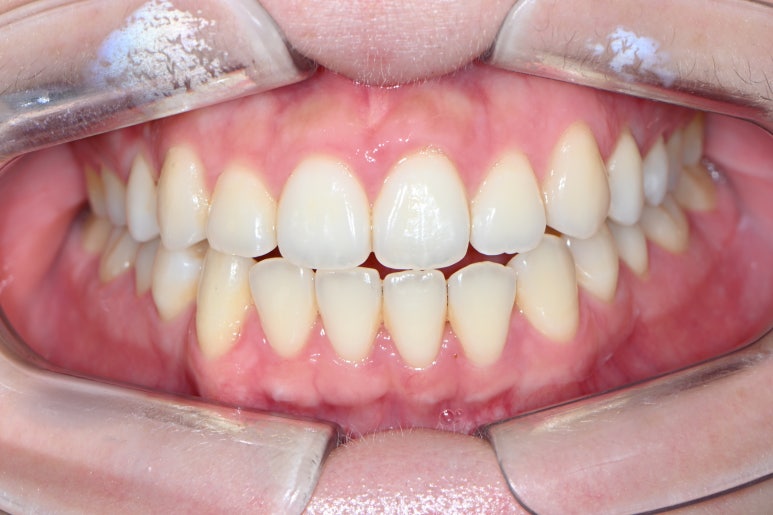

치아가 비교적 가지런한 편이지만, 약간은 노랗게 보이는 치아를 밝고 싶다는 이유로 오신 분이었어요.

요새 저희 논현동 레브치과가 치아미백 핫플인거 아시죠? ㅎㅎ 진짜 병원에 있는 치아미백 기계를 풀로 돌려도 손이 모자랄 정도......

치아 미백을 받으러 오신 분들은 이렇게 치아 색상표를 함께 두고 상담을 합니다.

보통 한국사람 치아는 A1,A2,A3,A3.5 등등 A계열의 색상이 많은 것 같아요~

참고로 숫자가 클수록 치아는 어두워집니다.